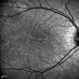

Chronic Full Thickness Macular Hole

full thickness macular hole, IR

Chronic full thickness macular hole OS, S/P attempted repair.